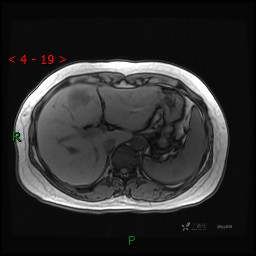

动态增强(动脉早期、动脉晚期、门脉期)